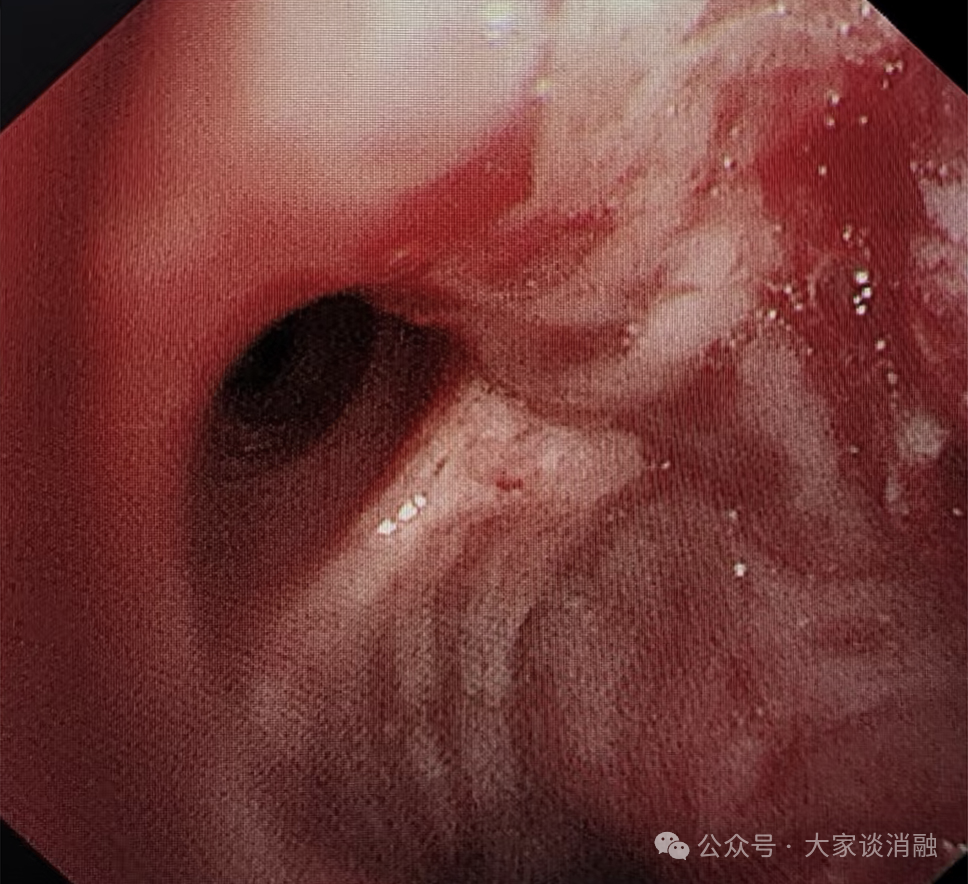

10月22日,患者接受第一次PTS治疗,在呼吸内二科邵桂英主任的精细操作下,全程顺利治疗后气道内肿瘤缩小达30%,患者呼吸困难症状大大缓解。

术前